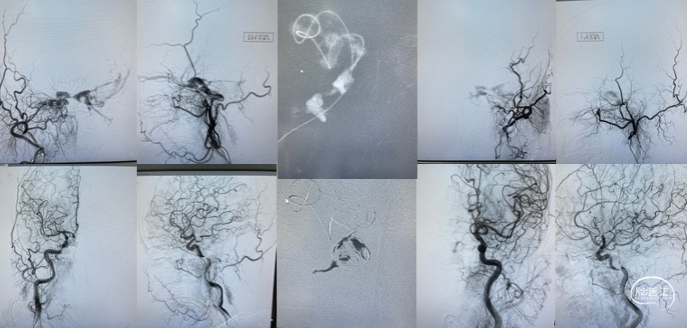

根据病史及当地医院辅助检查,诊断后颅窝硬脑膜动静脉瘘明确。分析当地医院MRA及血管造影结果,大致可判断该患者瘘口位于左侧舌下神经管或髁前汇区。详细读片可见左侧颈外动脉造影及椎动脉造影所示引流模式相同。入院后完善脑血管造影检查,并应用双容积影像后处理技术进行三维重建(图3)。便于进一步分析血管构筑,制定手术策略。

根据患者术前血管造影表现,该例病例确诊为左侧舌下神经管区硬脑膜动静脉瘘。分析其血管构筑特点:供血动脉为颈外动脉咽升动脉分支,椎动脉脑膜支,瘘口位于左侧舌下神经管区,经岩下窦向同侧海绵窦-海绵间窦-对侧海绵窦引流,并经髁前静脉向椎旁及椎管内静脉引流。患者有显著的搏动性耳鸣症状,且引流静脉具有出血风险,手术指征存在。笔者所在的中心既往诊疗的病例表明,舌下神经管的引流模式多种多样,但多数可见髁前静脉向岩下窦汇合。该患者亦有此静脉引流通道(图3黄色箭头所示),因此介入栓塞的路径上可考虑经要岩下窦-髁静脉路径。

术中将导引导管置于左侧颈内静脉,并引导至左侧岩下窦,Echelon-10微导管经由髁静脉超选至瘘口处。微导管到位后再次进行双容积三维后处理,验证微导管到位位置为术前所判断的瘘口处(图4),随后在瘘口放置一枚弹簧圈,并在阴性路图下注入Onyx胶0.8ml(图5)。复查造影见瘘口完全栓塞,异常引流彻底消除(图6)。

栓塞术后即刻CT未见颅内出血或Onyx胶异位栓塞。麻醉复苏后患者诉耳鸣消失,未诉其他不适,查体无新发神经系统体征。术后第二日,复查CT未见异常(图7),患者顺利出院。

患者术后半年于当地医院复查血管造影,提示瘘口完全栓塞,未见复发(图8)。

图8. 术后半年复查脑血管造影。